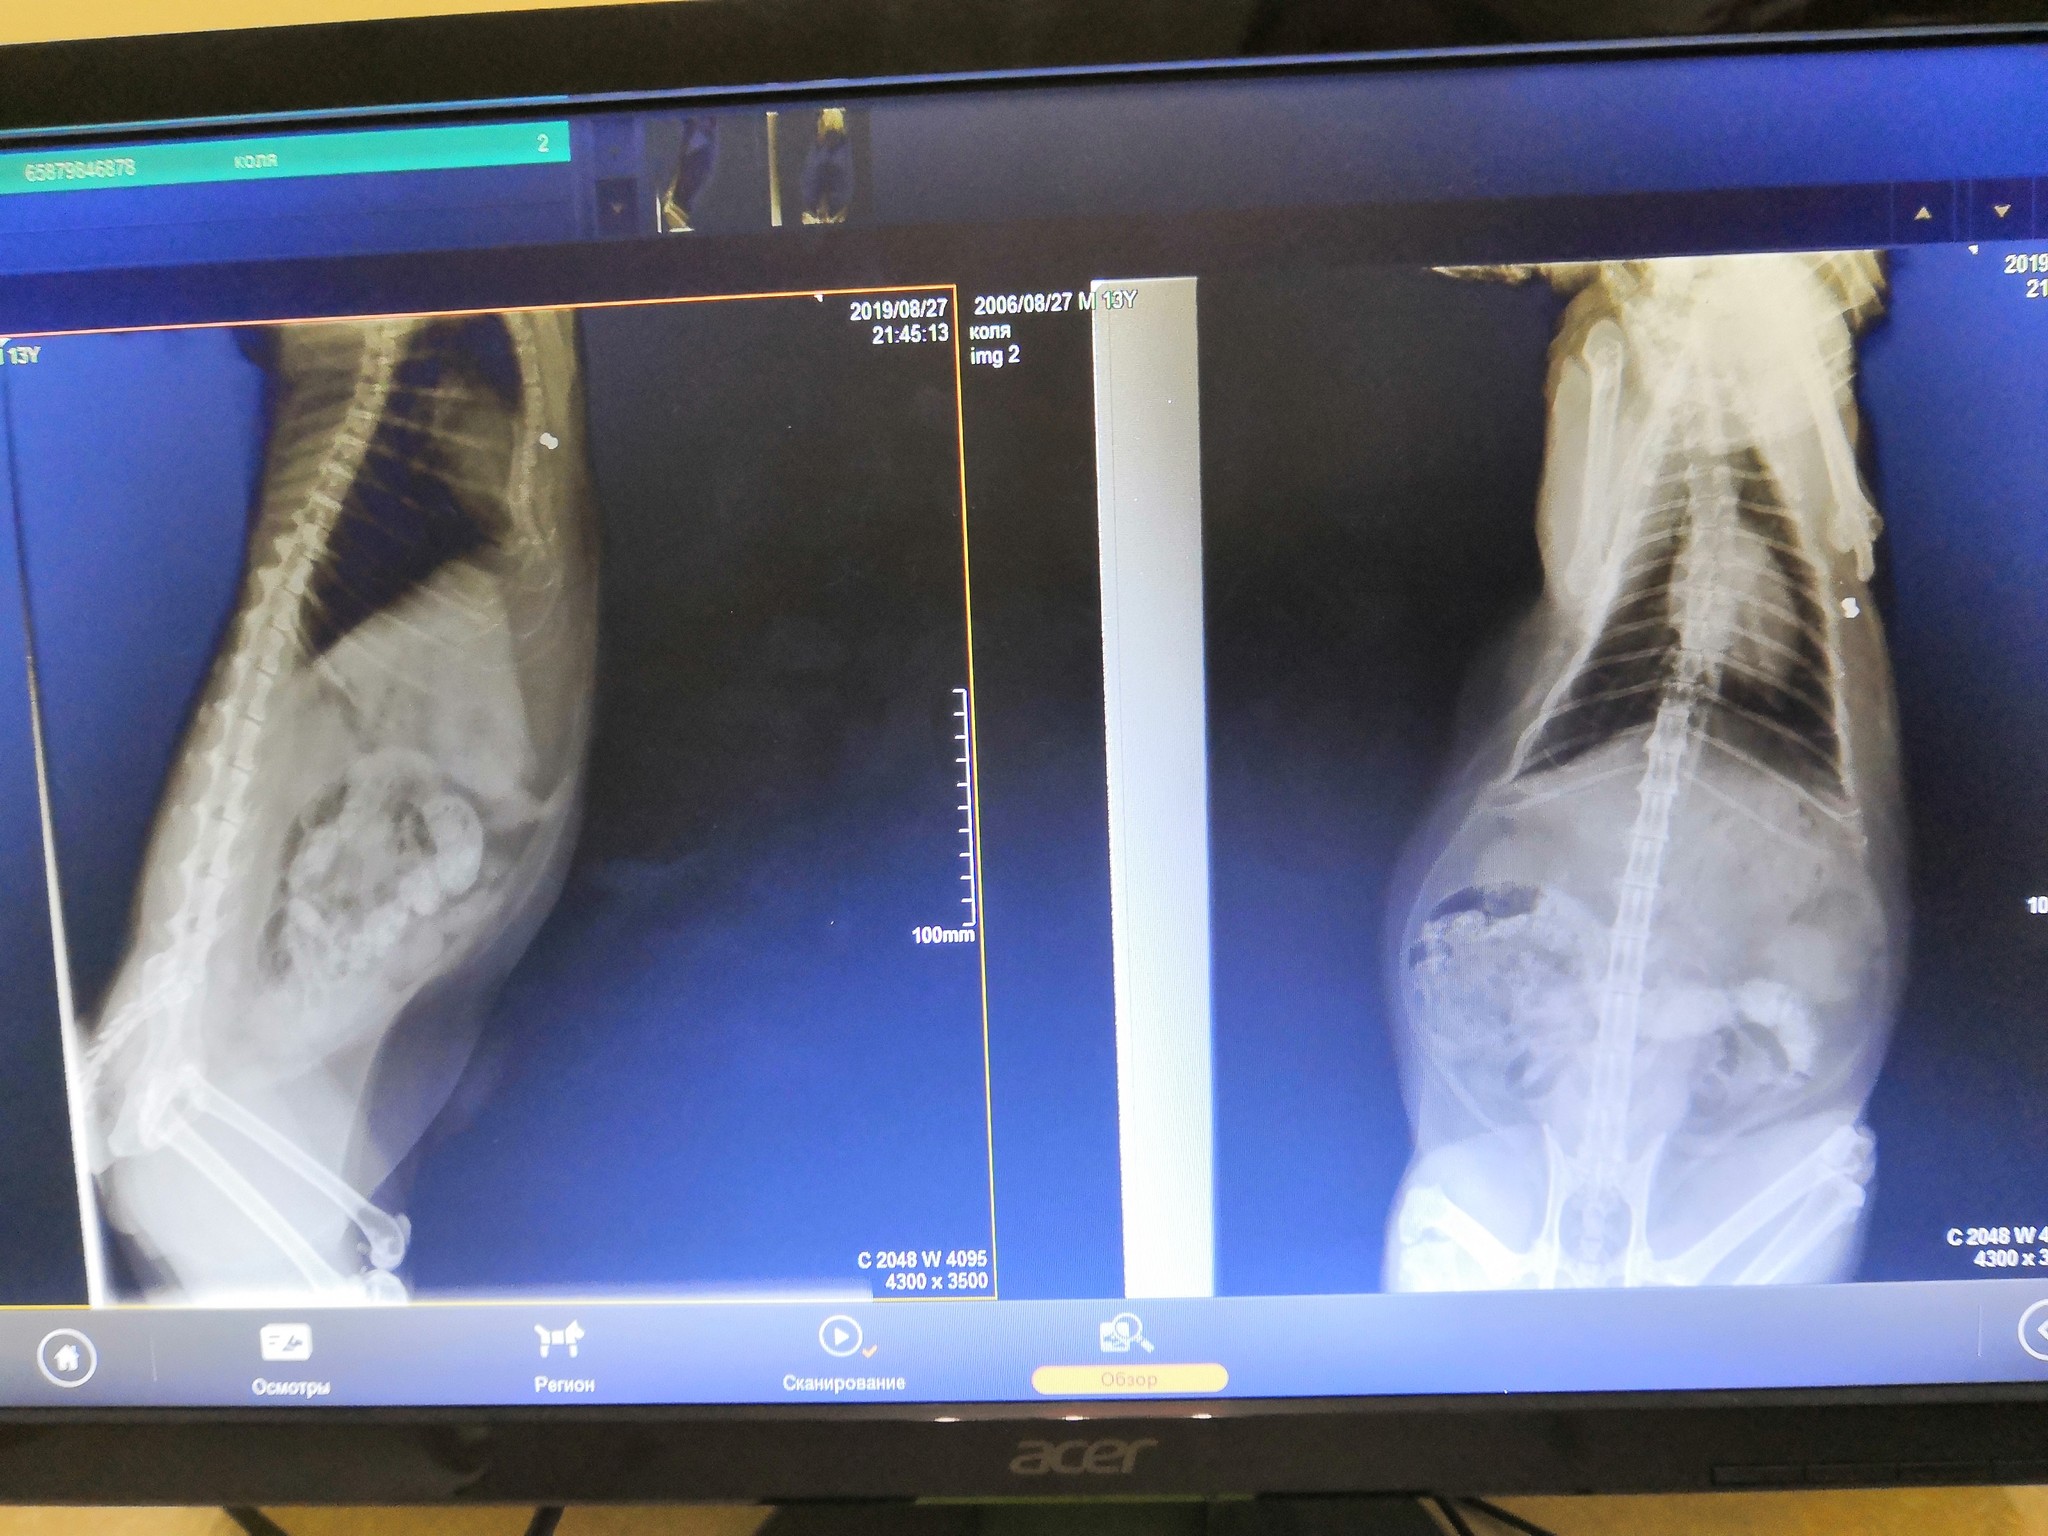

Ради интереса и полноты картины решили сделать рентген

Я замер, сердце начало дубасить, я моргал пытаясь развидеть, но не получилось

Маленькая белая точка была подозрительно похожа на пульку воздушки (дед был инструктором по стрельбе).

В добавок к этому, друг показал на старый перелом грудины.

сделали второй снимок

Начали прощупывать, нашли уплотнение от которого кот приходил в бешенство при попытке более тщательно потрогать.

Вердик был краток: Было, зажило, сейчас ничего не нужно кроме диеты. Пулька снаружи грудной, с этим живут и не переживают. Приходи через месяц посмотрим что будет.